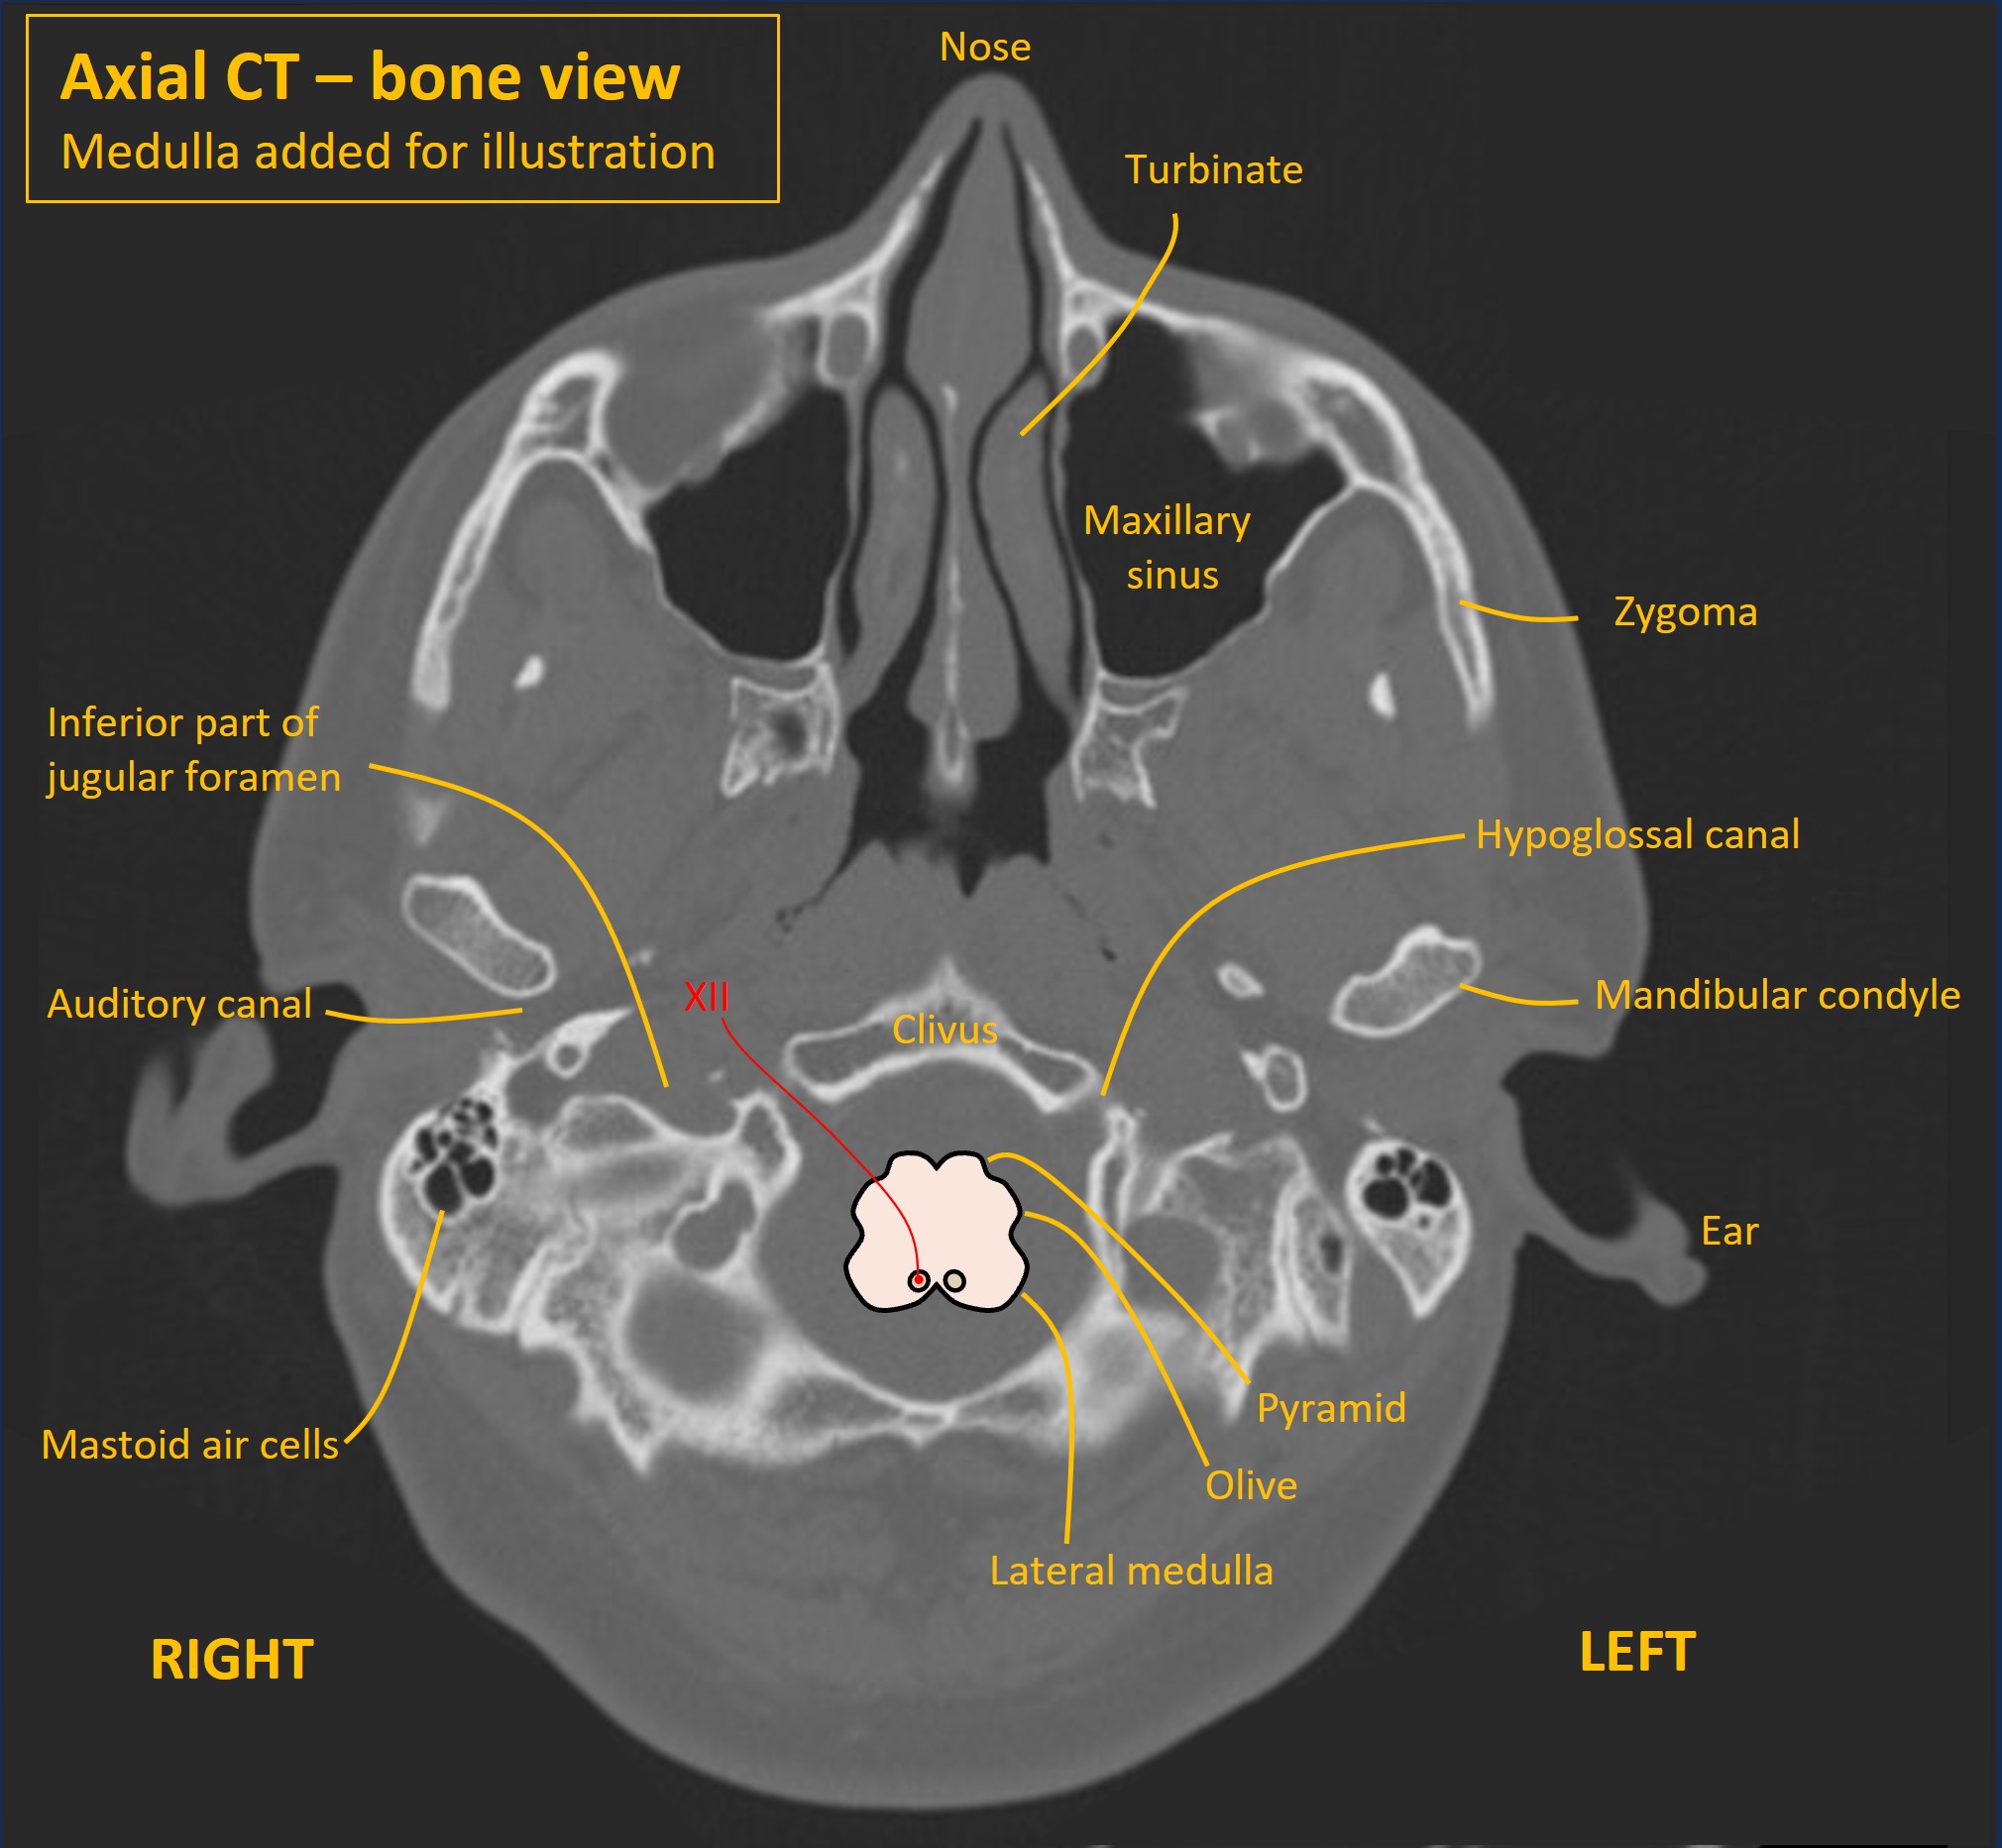

The fascicles of XII run anteriorly and laterally on an angle, between the inferior olive and the pyramids, and the nerve exits the brainstem between these. It travels anteriorly to the medulla in the premedullary cistern (subarachnoid space), then pierces the dura and exits the cranial cavity via the hypoglossal canal in the skull base (occipital bone), lateral to the foramen magnum.

A CT scan shows this below.